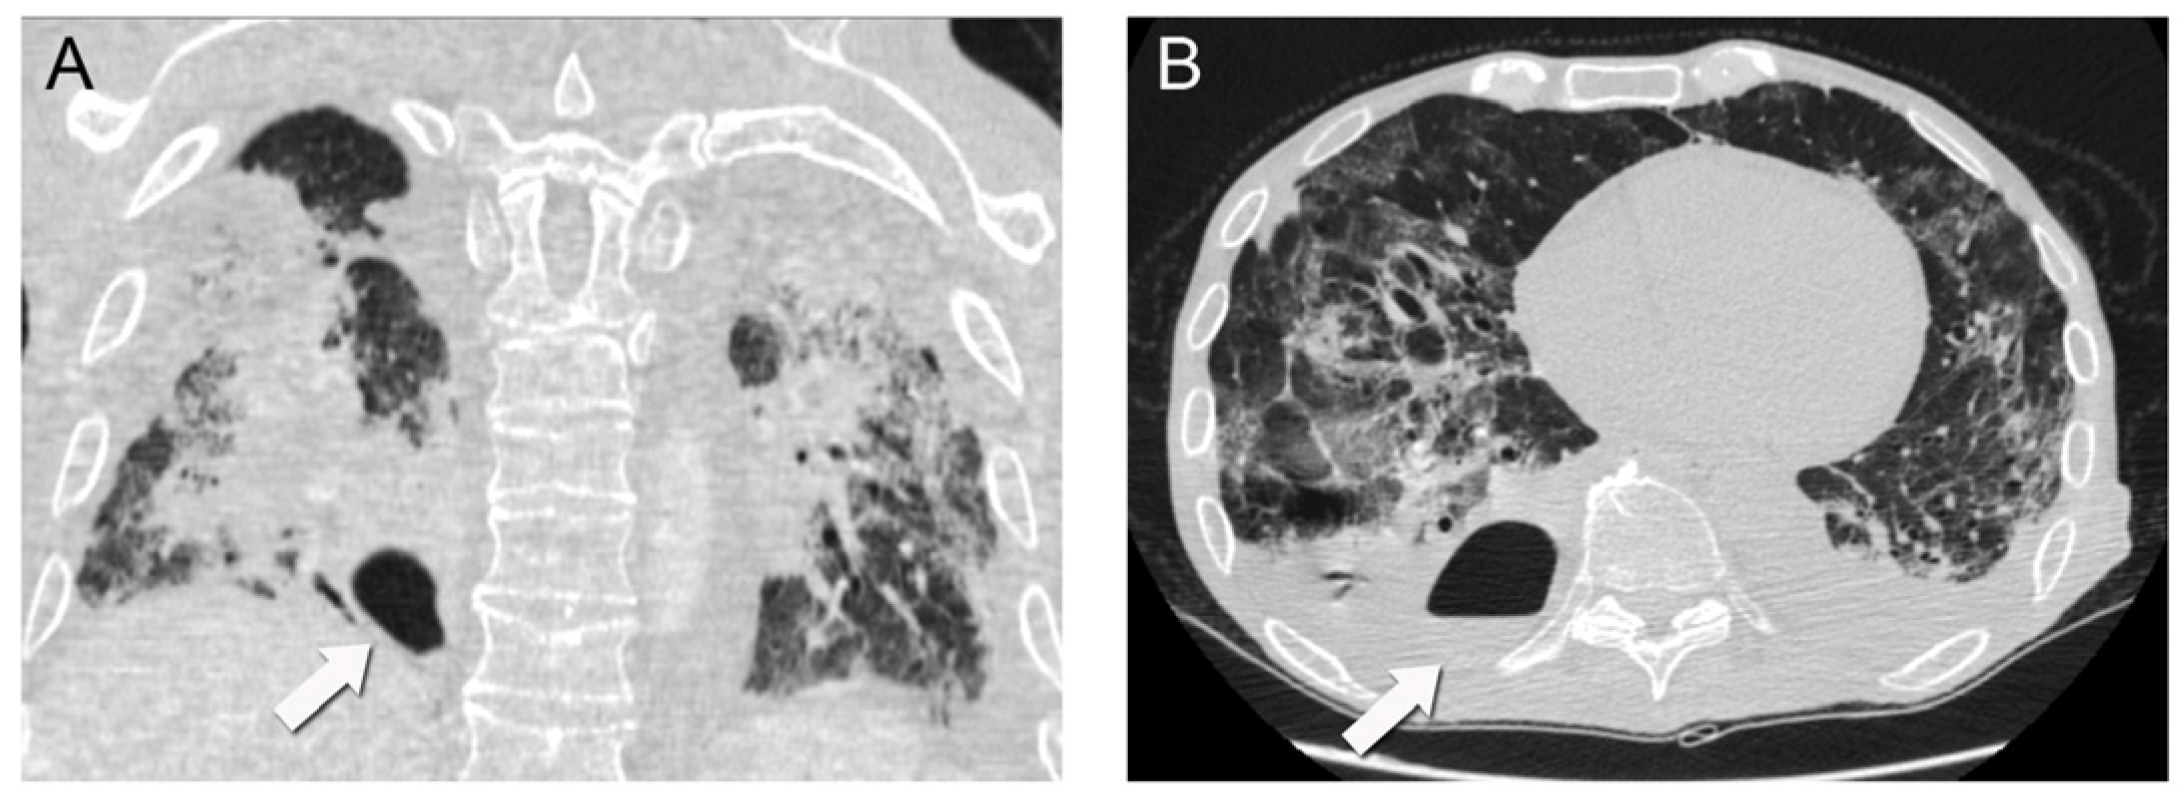

Laboratory investigations showed normal lymphocyte count with neutrophilia (89%) and severe lymphopenia (4.9%), increased C reactive protein (CRP) at 10.3 mg/L and normal procalcitonin (PCT) at 0.82 µg/dL. The rest of his laboratory values were within the normal range. His chest X-ray on admission presented with extensive consolidation and infiltrates mainly in the lower lung fields with blunting of the costo-diaphragmatic angles. His admission chest computed tomography (CT) scan demonstrated extensive ground glass infiltrates and diffuse consolidation bilaterally with a focus on the right lower lobe (Figure 1).

The patient’s initial chest CT demonstrated significant areas of diffuse consolidation and patchy ground glass opacification. These are findings which have previously been associated and described with COVID-19 viral pneumonia [7]. In addition, in hindsight there seemed to be a focus of atelectasis and consolidation in the right lower lobe which could represent the precursor of the lung abscess.

Figure 1. Initial (on admission) chest computed tomography scan in coronal (A) and axial (B) views demonstrating extensive bilateral areas of consolidation and ground glass infiltrates, with lung cavitation mainly on the posterior segment of the right lower lobe.